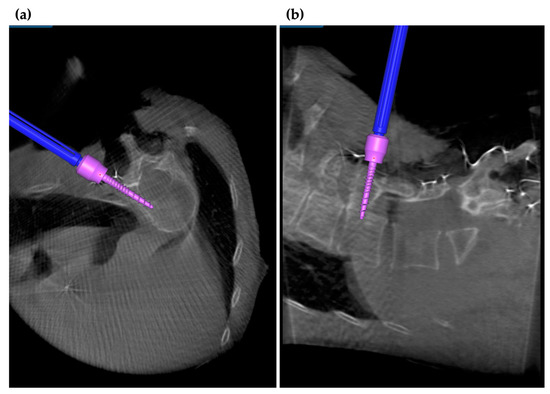

3.3. Application of Navigation Systems in Cervical Spine Surgery

3.6. Robotics-Assisted Surgery